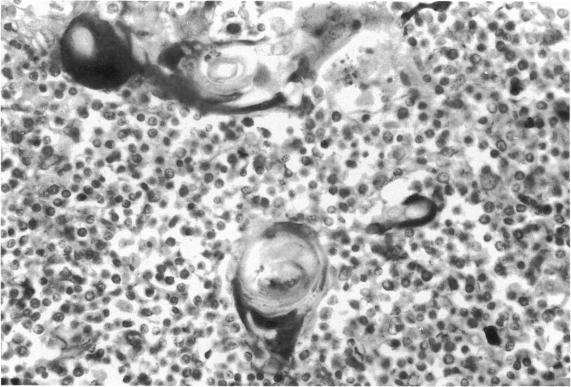

人胸腺哈氏小体内的免疫球蛋白

Immunoglobulins in Hassall's corpuscles of the human thymus.

Ninety nine human thymuses were examined immunohistochemically for the presence of immunoglobulins G, A, M. D and E, light-chains, secretory component and albumin in the cells of Hassall's corpuscles. Igs G, A, M and secretory component were present. These showed a rise after birth until the age of 20 years and also increased with the degree of involution, falling when involution became complete. Albumin was also consistently demonstrated. There was a degree of correlation between the presence of Igs and production of Igs G, A and M by plasma cells in the thymic medulla. There was a close correlation between the amounts of IgA and secretory component in the cells of Hassall's corpuscles and the thymus may have to be regarded as a part of the secretory-IgA system. Light chains of the immunoglobulin molecule were also present, with lambda predominating over kappa, possibly reflecting the same kappa/lambda ratio found with thymic immunoglobulin production. No IgD or IgE was demonstrated. The presence of albumin may represent a passive uptake of protein in senescent cells but a more active uptake of Igs, particularly IgG and IgA, could be postulated. The production of Igs in the thymus and their presence in Hassall's corpuscles could be of significance in the maturation and regulation of the immune response.

摘要